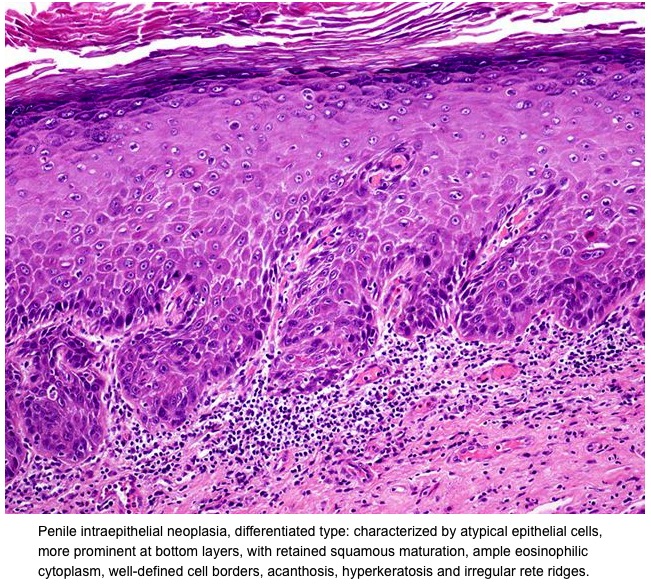

List showcases captivating images of penile cancer photos download gathered and meticulously curated by the website galleryz.online. Furthermore, you can find more related images in the details below.

penile cancer photos download

Posts: penile cancer photos download